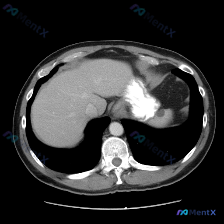

上腹部横断面CT(软组织窗),患者口服了对比剂(胃腔内高密度影为造影剂留影)。

- 肝脏:实质密度均匀,未见明确占位,肝叶比例、形态大致正常;

- 脾脏:划重点——形态规则,密度均匀,没有局灶性低密度/高密度灶,没有脾大,也没有脾周积液;

- 胃:胃腔内有造影剂充盈,但在胃体后壁/胃底区域,能看到局部胃壁不规则增厚,而且边界欠清晰;

- 其他:腹主动脉等大血管走行、管径正常;胃周及腹腔脂肪间隙清晰,未见明显渗出;椎体及后腹膜结构也未见明确骨质破坏或巨大肿块。